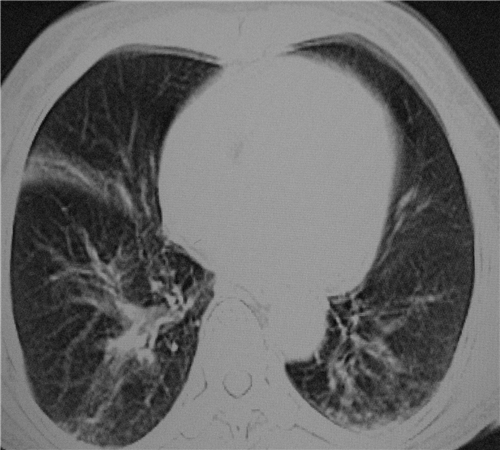

标题: CT26849:女67岁反复胸痛两天余,临床考虑夹层。 [打印本页]

标题: CT26849:女67岁反复胸痛两天余,临床考虑夹层。

双下肺感染,右侧显著。有无夹层,增强扫描后再诊断。

1.考虑双肺感染,右侧为重;2.建议ct增强或mri排除主动脉夹层

双下肺感染,右侧显著。有无夹层,增强扫描后再诊断。食道未见异常。